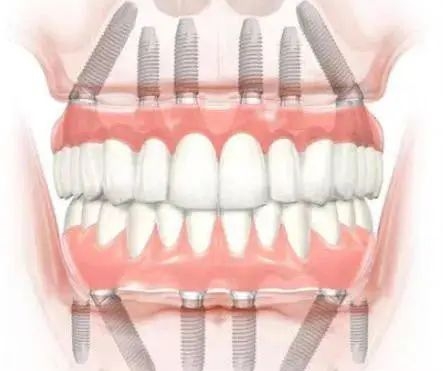

值得注意的是,60歲以上老年患者憑有效身份證件可享受種植牙項(xiàng)目9折優(yōu)惠,同時(shí)醫(yī)院還提供分多次付款服務(wù),減輕患者經(jīng)濟(jì)壓力。對(duì)于全口或半口牙缺失患者,醫(yī)院推出All - on - 4等綜合治療方案,價(jià)格16990元起,相比單顆種植可節(jié)省約30%費(fèi)用。